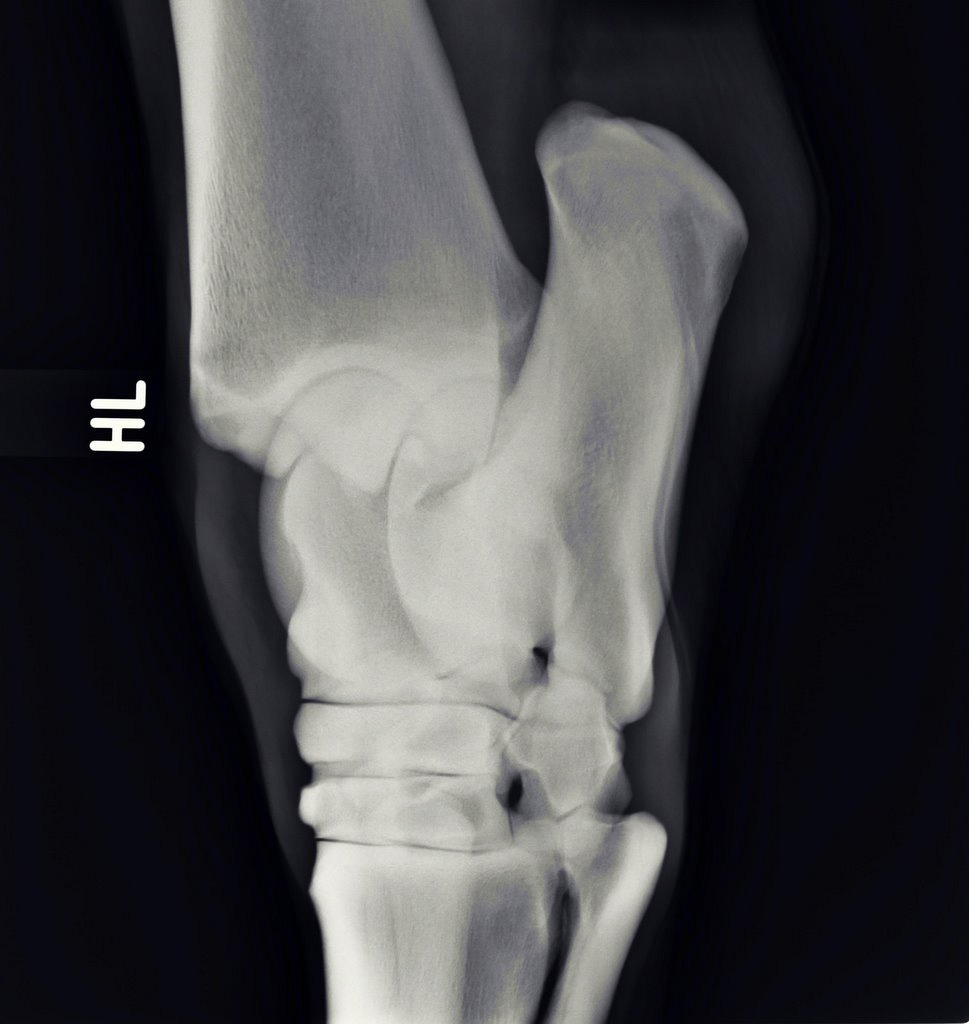

Illustrative Mindeststandardaufnahmen zur Beurteilung nach dem Röntgenleitfaden: